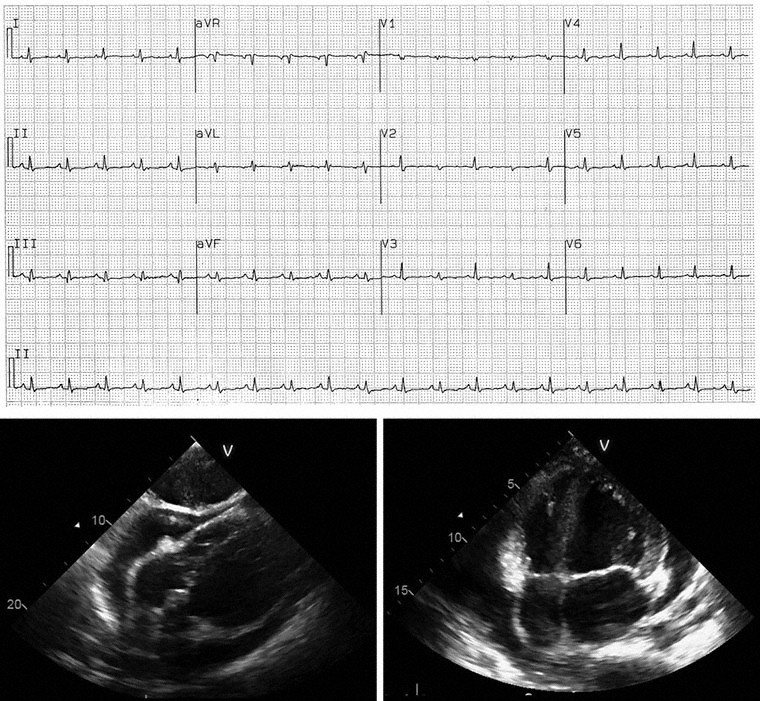

A 27-year-old man comes to the physician because of an 8-month history of shortness of breath with exertion. He has a 1-week history of mild shortness of breath after climbing one flight of stairs. He has not had fever, cough, or weight loss. He does not smoke. He is employed as an office worker. Vital signs are within normal limits. Jugular venous pressure is 7 cm H2O. There is clubbing of the fingers bilaterally. Crackles are heard throughout the lungs. Arterial blood gas analysis on room air shows:

An x-ray of the chest is shown. Pulmonary function tests show a normal FEV1:FVC ratio and decreased diffusion capacity of the lung for carbon monoxide. Which of the following is the most likely explanation for this patient’s dyspnea?